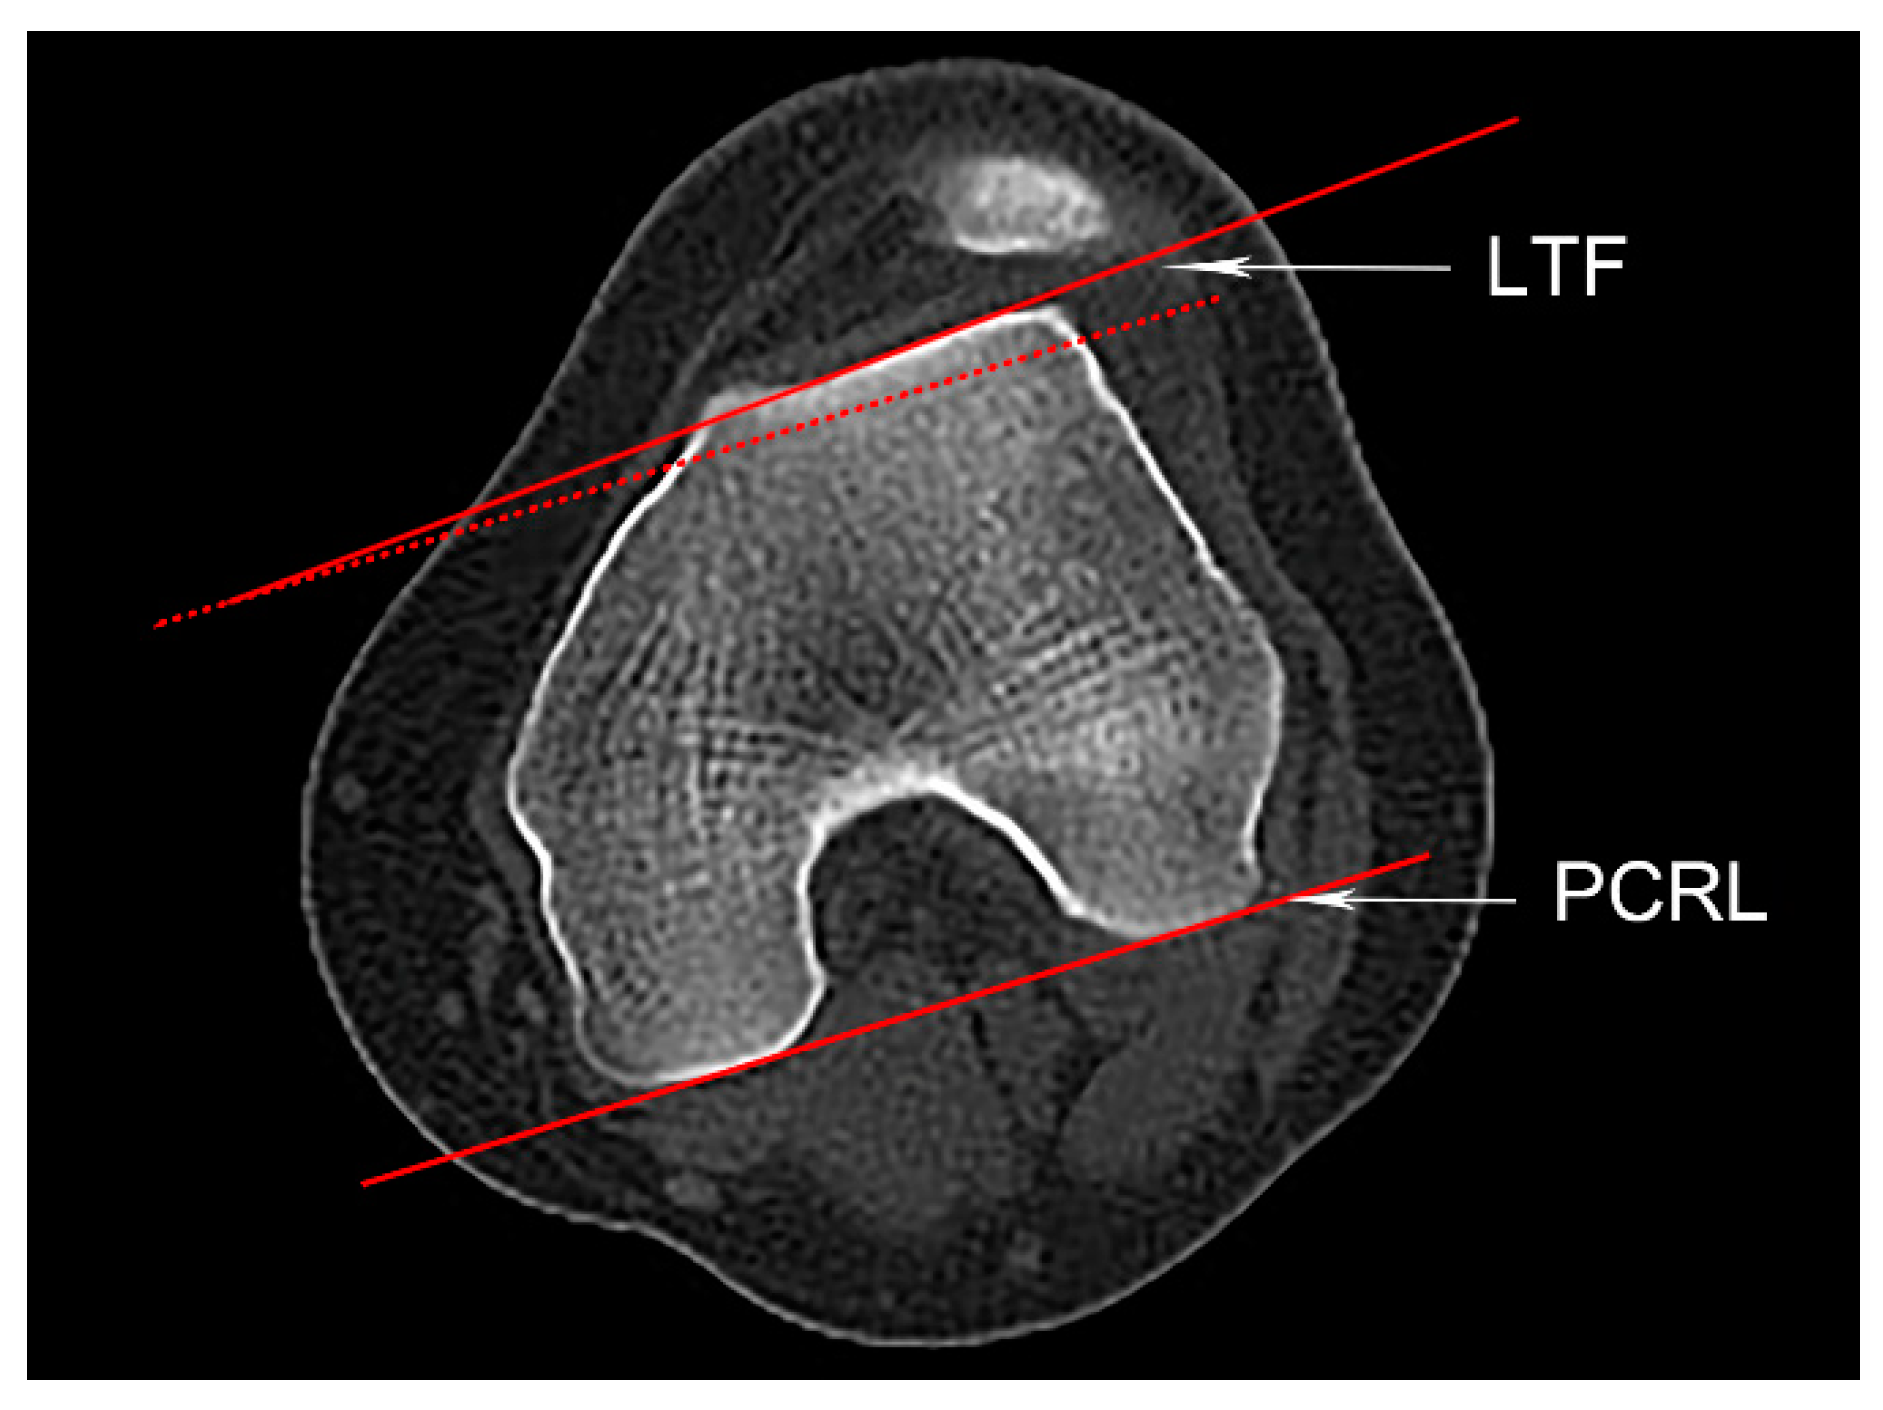

2.4.1. Femoral Anteversion

2.4.2. Trochlear Dysplasia

2.4.3. TT-RA Distance